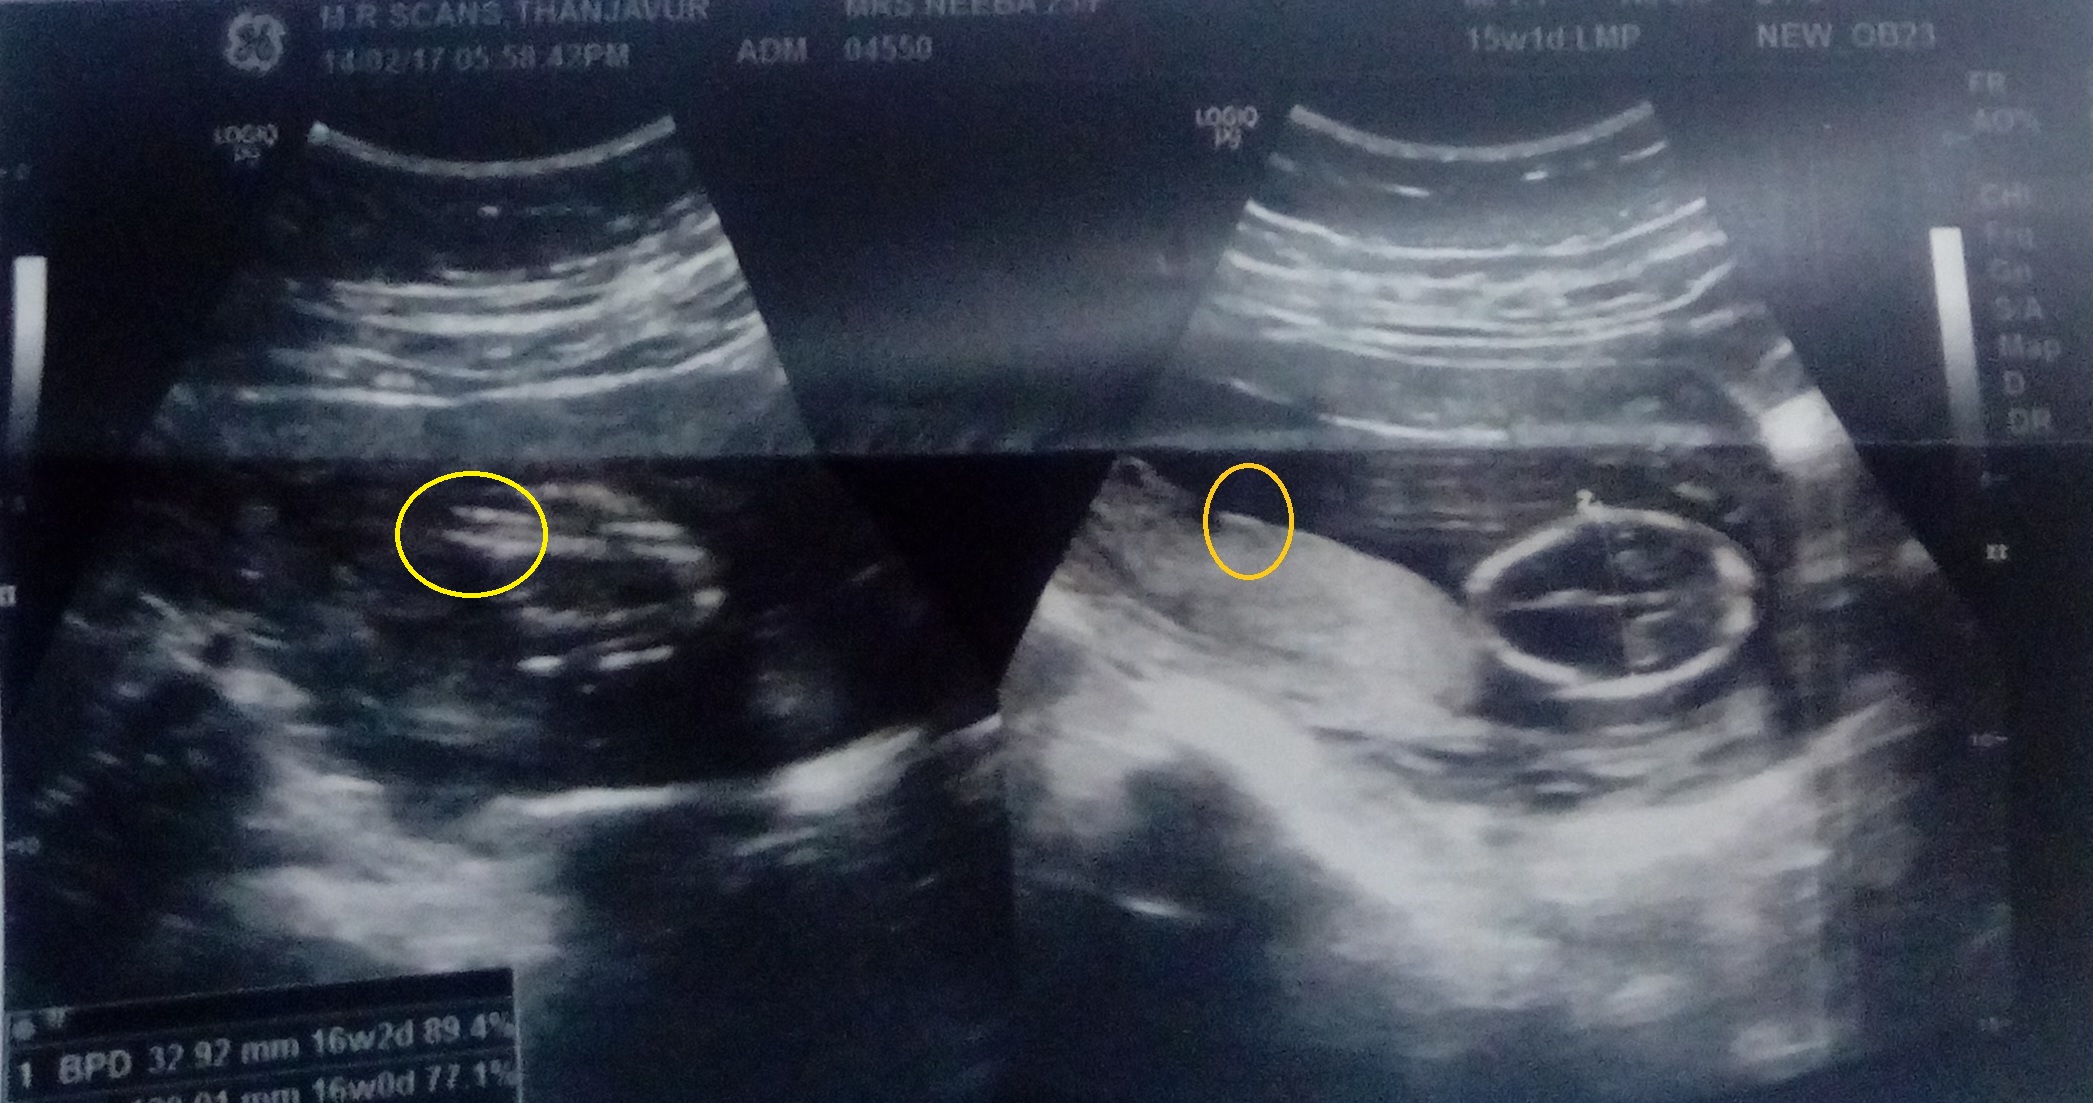

and another one, all of the images were taken at 15 weeksAttachment 35439

I think the only one that MAYBE shows gender is the second to last pic (the one on the left). Maybe girl, but there is writing there covering the gender, so I'm not sure.

Not seeing any gender clues and nub isn't an indicator at 15 weeks anyway, you'd need a potty shot x